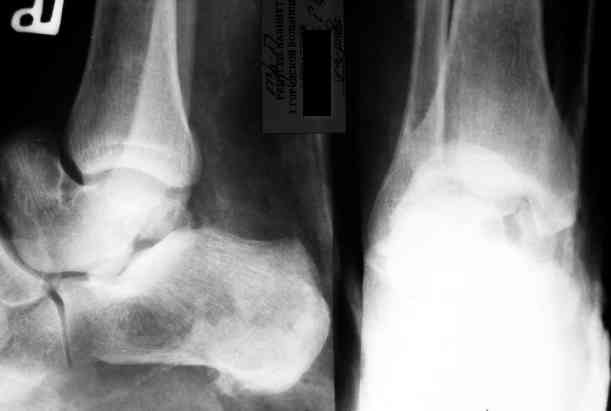

Уважаемый Александр! Как обещал представляю Р-граммы и операционные фото.

Ваши (лично ваши) рекомендации - астрагалэктомия-аппаратный пяточно-большеберцовый артродез с одновременным удлинением голени - правильно?

А> Ваши (лично ваши) рекомендации - астрагалэктомия-аппаратный

А> пяточно-большеберцовый артродез с одновременным удлинением голени - правильно?

Да.

Насколько я понял, критической ишемии ведь нету?

При обычном для удлинения темпе должен быть обычный регенерат.

Мы обычно удлиняли на 2 уровнях по 1,5-2 см. В конце концов, можно и не удлинять, укорочение компенсировать вкладками в обувь.